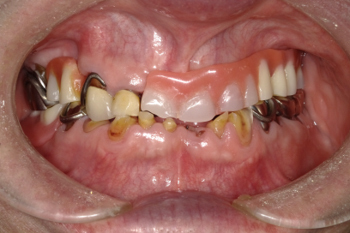

症例

50代男性。全顎的な虫歯と歯周病を治療した症例。

治療後

治療内容:噛み合わせの高さが低下し、ほぼすべての歯が虫歯と歯周病になっていたため、歯茎の治療を行った上で、審美的な被せものを製作しました。

治療期間:約12か月間

リスク・副作用:経年的な顎骨の吸収に対する調整の必要性、義歯を装着している違和感など